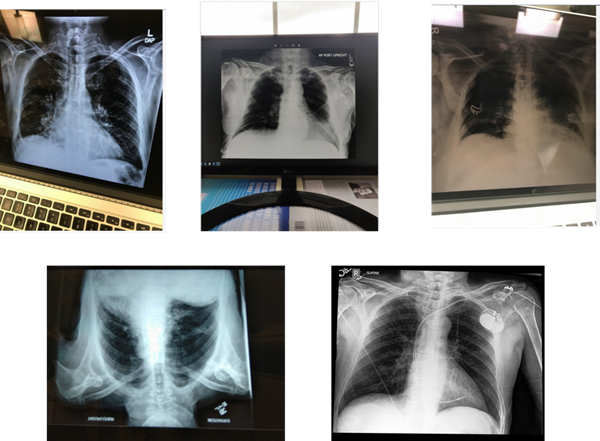

The dataset used in this study is supplied by the CheXPhoto 2020 competition [24]. The competition provides a training set including natural and synthetic transformations of 10,507 xrays taken from 3000 unique patients sampled from the original CheXpert dataset [24]. The provided validation set which consists of 244 x-rays is taken for self-evaluation and hyperparameter tuning purposes. Visualized examples from the CheXphoto dataset is shown in figure 1.

Refer to caption

Figure 1: Examples from the CheXPhoto dataset